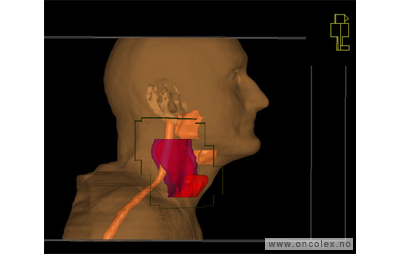

Skisse over hvordan strålefeltet planlegges:

Illustrasjon for målvolum

• GTV (Gross Tumor Volume): Identifisert tumor.

• CTV (Clinical Target Volume) GTV + omkringliggende vev hvor det kan væremikroskopisk spredning.

• ITV (Internal Target Volume): CTV + en indre margin som tar hensyn tilindre bevegelser og endringer av CTV.

• PTV (Planning Target Volume): Innstillingsmargin som inneholder ITV og samtidig tar hensyn til antatte pasientbevegelser, samt variasjoner i pasientopplegging og feltinnstillinger.

• Feltgrense. Tegnes som oftest på kroppen.

ICRU (International Commission on Radiation Units and Measurements)